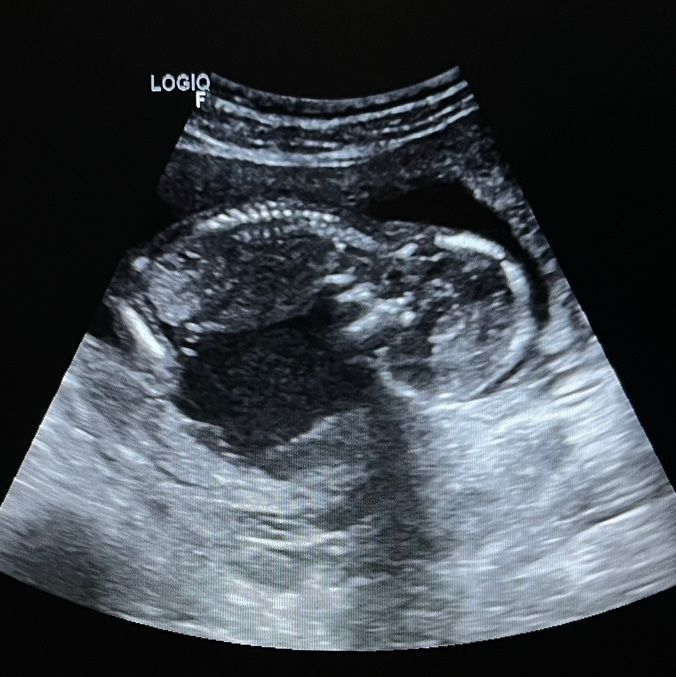

Узи 15 недель 5 дней